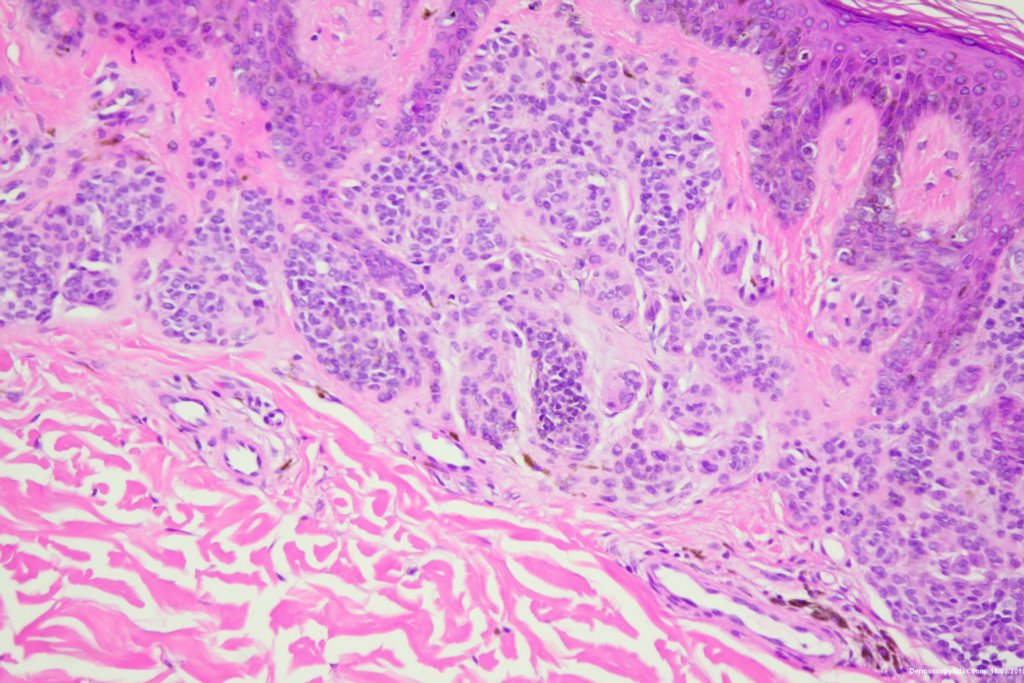

Diagnosis: Nevus compound

A pigmented lesion on the ankle which showed some grey dots suggesting regression and a slightly thickened network in parts.

Histology showed a compound nevus with some pigment in melanophages in the dermis giving the grey.